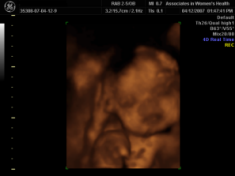

New Ultra sound PIcs...

I had a 4-D one done today. It's kinda small where I've resized it, but I think you can still see. I'm getting it re done in 3 wks to see if she'll cooperate more.